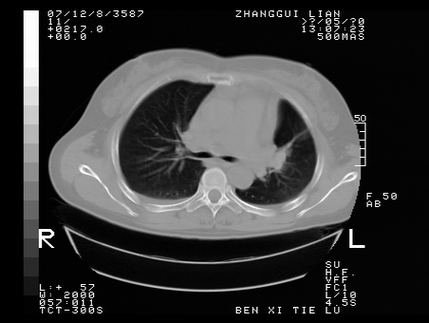

标题: CT10817:女,46,胸疼,无其他病史 [打印本页]

标题: CT10817:女,46,胸疼,无其他病史

左侧上纵隔旁团块影,部分植入纵隔,与纵隔界限不清,另:左肺门明显见团块,气管隆突前方见肿大淋巴结。考虑:左上肺纵隔型肺癌伴左肺门及纵隔淋巴结转移!

首先考虑左侧中央型肺癌伴阻塞性肺炎、纵隔内、弓旁淋巴结转移可能性大(纵隔窗调的欠佳)

1左上肺中心型肺癌伴左肺上叶不张2主动脉弓旁淋巴结转移3左下肺炎症

1 左侧中央型肺癌伴阻塞性肺炎 2 左肺门及纵隔淋巴结转移!3两侧胸腔及心包积液.

左侧胸廓塌陷,纵隔向左侧移位,左上肺不张。